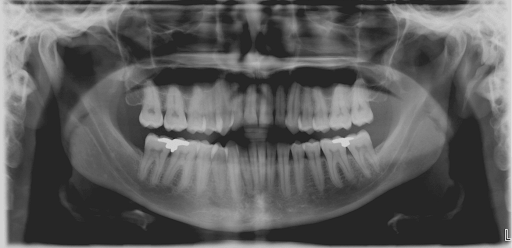

Panoramic Radiograph

We have panoramic and cephalomatric radiographs. With panoramic radiographs, we can see all teeth and bone surrounding teeth, cyst or tumor of the jaw or sinuses. We can assess bone level between teeth or infection at the root of teeth.